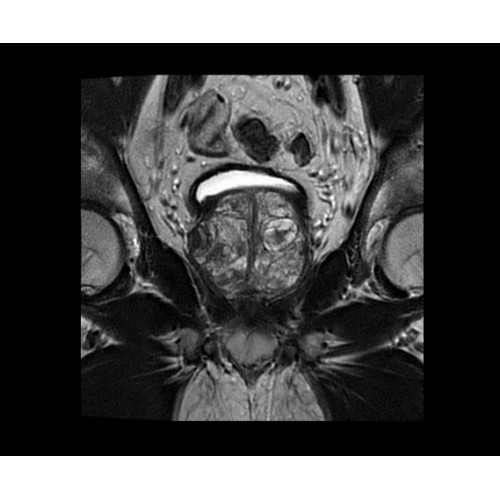

SIGNA PET/MR 3.0T — это гибридная система, в которой совмещаются две принципиально разные технологии — магнитно-резонансную томографию (МРТ) и позитронно-эмиссионную томографию (ПЭТ). Система отличающийся высокой чувствительностью и эффективностью и предназначена для диагностики в области онкологии, неврологии, кардио-васкулярных исследований, исследований воспалительных процессов.

Компания GE Healthcare представляет революционную, полностью интегрированную систему SIGNA PET/MR1, в которой сочетаются времяпролетная технология (TOF) и возможности напряженности магнитного поля 3.0 Тл. Мы поможем вам поднять исследования на более высокий уровень. SIGNA PET/MR позволяет достичь впечатляющей точности и скорости исследований, а благодаря новейшей технологии реконструкции Q.Clear2 качество изображений улучшается в два раза. Кроме того, в систему включен полный набор клинических приложений и гибких катушек для проведения любых видов исследования, открывая для вас возможности визуализации, о которых вы даже не догадывались.

В систему SIGNA PET/MR встроены запатентованные детекторы кремниевого фотоумножителя (SiPM) и сверхчувствительные кристаллические сцинтилляторы на основе лютеция толщиной 25 мм. Благодаря этому обеспечивается исключительная чувствительность и возможность использования времяпролетной диагностики (TOF).

Кроме того, в результате использования технологии TOF и инновационной технологии реконструкции Q.Clear вы сможете добиться прекрасного соотношения сигнал/шум. А благодаря технологии нулевого времени эхо (ZTE) визуализировать костную структуру без ионизирующего излучения. Все эти разработки для улучшения качества сканирования и точности анализа помогут вам использовать весь потенциал ПЭТ/МРТ.

• TurboTOF — инновационная технология позволяет корректировать коэффициент затухания сигнала и минимизировать потери анатомических данных, создавая МР-систему для количественной визуализации.

• Q.Clear — в основу технологии легли накопленные знания о том, как минимизировать помехи при реконструкции и получить четкое изображение. При значительном улучшении качества изображения сохраняется точность расчетов. Сочетание технологии TOF и реконструкции Q.Clear — ваш надежный помощник для получения точных и достоверных данных.

• МРТ с функцией нулевого времени эхо (ZTE) отличается точностью, возможностью персональных настроек и отсутствием ионизирующего излучения. Она приходит на смену традиционному исследованию на основе рентгеновского излучения. МРТ с функцией нулевого времени эхо (ZTE) на базе SIGNA ПЭТ/МРТ является более надежной и быстрой по сравнению с системами, использующими сверхмалое время эхо (UTE).